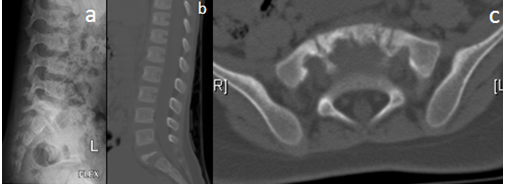

Lumbosacral x-ray showed a destructive lesion of the sacrum with loss of vertebral height and sclerosis, figure (3 a), skeletal survey didn’t demonstrate any other lesion in the skeleton.

The patient was admitted to the hospital for further investigation and management, MRI with contrast showed a lesion occupying S1 bright on T2 weighed images and dark on T1 weighed images and mixed stained with contrast no neurological compromise was seen, figure (4 a, b, and c), CT scan showed destruction of the body of the first sacral vertebra, posterior elements looks intact, Figure (3b and c), bone scan showed increase uptake in the body of S1 no other lesions.

Figure 3. AA images: a) lateral X-ray, b) CT scan sagittal images, c) CT scan Axial images